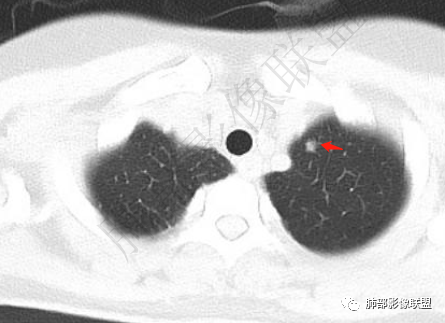

青年女性,胸痛1年,慢性病程

胸膜多个结节,附近胸壁脂肪间隙密度增高,提示有胸壁蔓延或侵犯。

一月后复查,肺内病灶密度增高,边缘收缩,体积缩小,提示渗出朝增生转变;胸膜病灶缩小。

1.胸膜多发结节,边缘比较光滑,累及胸壁(胸痛也符合,一年),表现为脂肪间隙密度增高,最大的病灶累及肺内,附近有渗出,但是无放射状表现,增强中央有坏死灶,一月后似有缩小,肋骨完整未见破坏,支持炎性可能大!